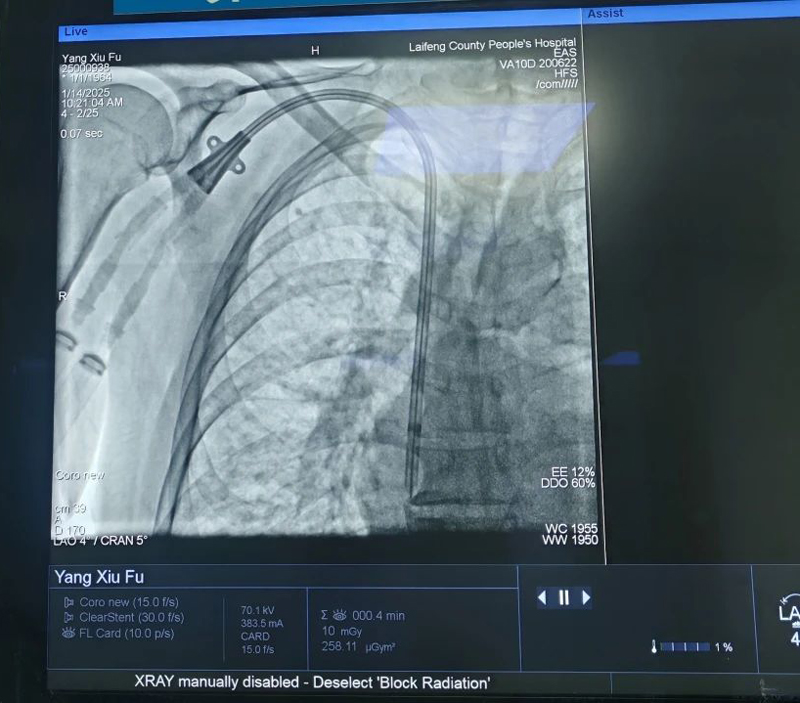

面对石大爷复杂的病情,医生们最终为石大爷选择了DSA下带涤纶套血液透析导管置入术。在DSA的实时监控引导下,肾内科医疗团队克服了动静脉相邻太近且有部分重叠的情况,成功地将导管植入王大爷体内。再次证明了DSA下带涤纶套血液透析导管置入术在复杂病例中的显著优势。

除了石大爷外,近期我院介入诊疗中心、肾内科在武汉市五医院李明梅主任的协助下联合为10例尿毒症患者成功实施了DSA引导下右侧颈内静脉长期透析导管置管术,为患者建立了长期性的血液透析通道,保证了患者的正常治疗。

尿毒症的治疗是长期性、连续性的。在成功开展“DSA引导下右侧颈内静脉长期管置管术”的10例患者中,其中两例患者均有糖尿病史,合并高血压、脑梗塞、心功能不全等疾病,长期在我院进行血液透析治疗。患者的血管条件极差,为建立安全可行的透析通路,在为患者完善各项检查后,龙静主任及武汉市五医院李明梅主任共同为患者实施了“DSA引导下右侧颈内静脉长期管置管术”。患者手术非常顺利,置管一次性成功,未出现出血及静脉阻塞等并发症,且导管末端位置良好,术后引血通畅、血流量好,能满足血液透析需求。

目前,我院采用的数字减影血管造影技术(DSA)引导下的穿刺技术,避免了血管损伤,可直观了解置入导管的位置,降低穿刺失败率和穿透血管壁等出血风险和意外发生,大大减轻了患者的痛苦及经济负担,为保证患者生命安全奠定了基础。